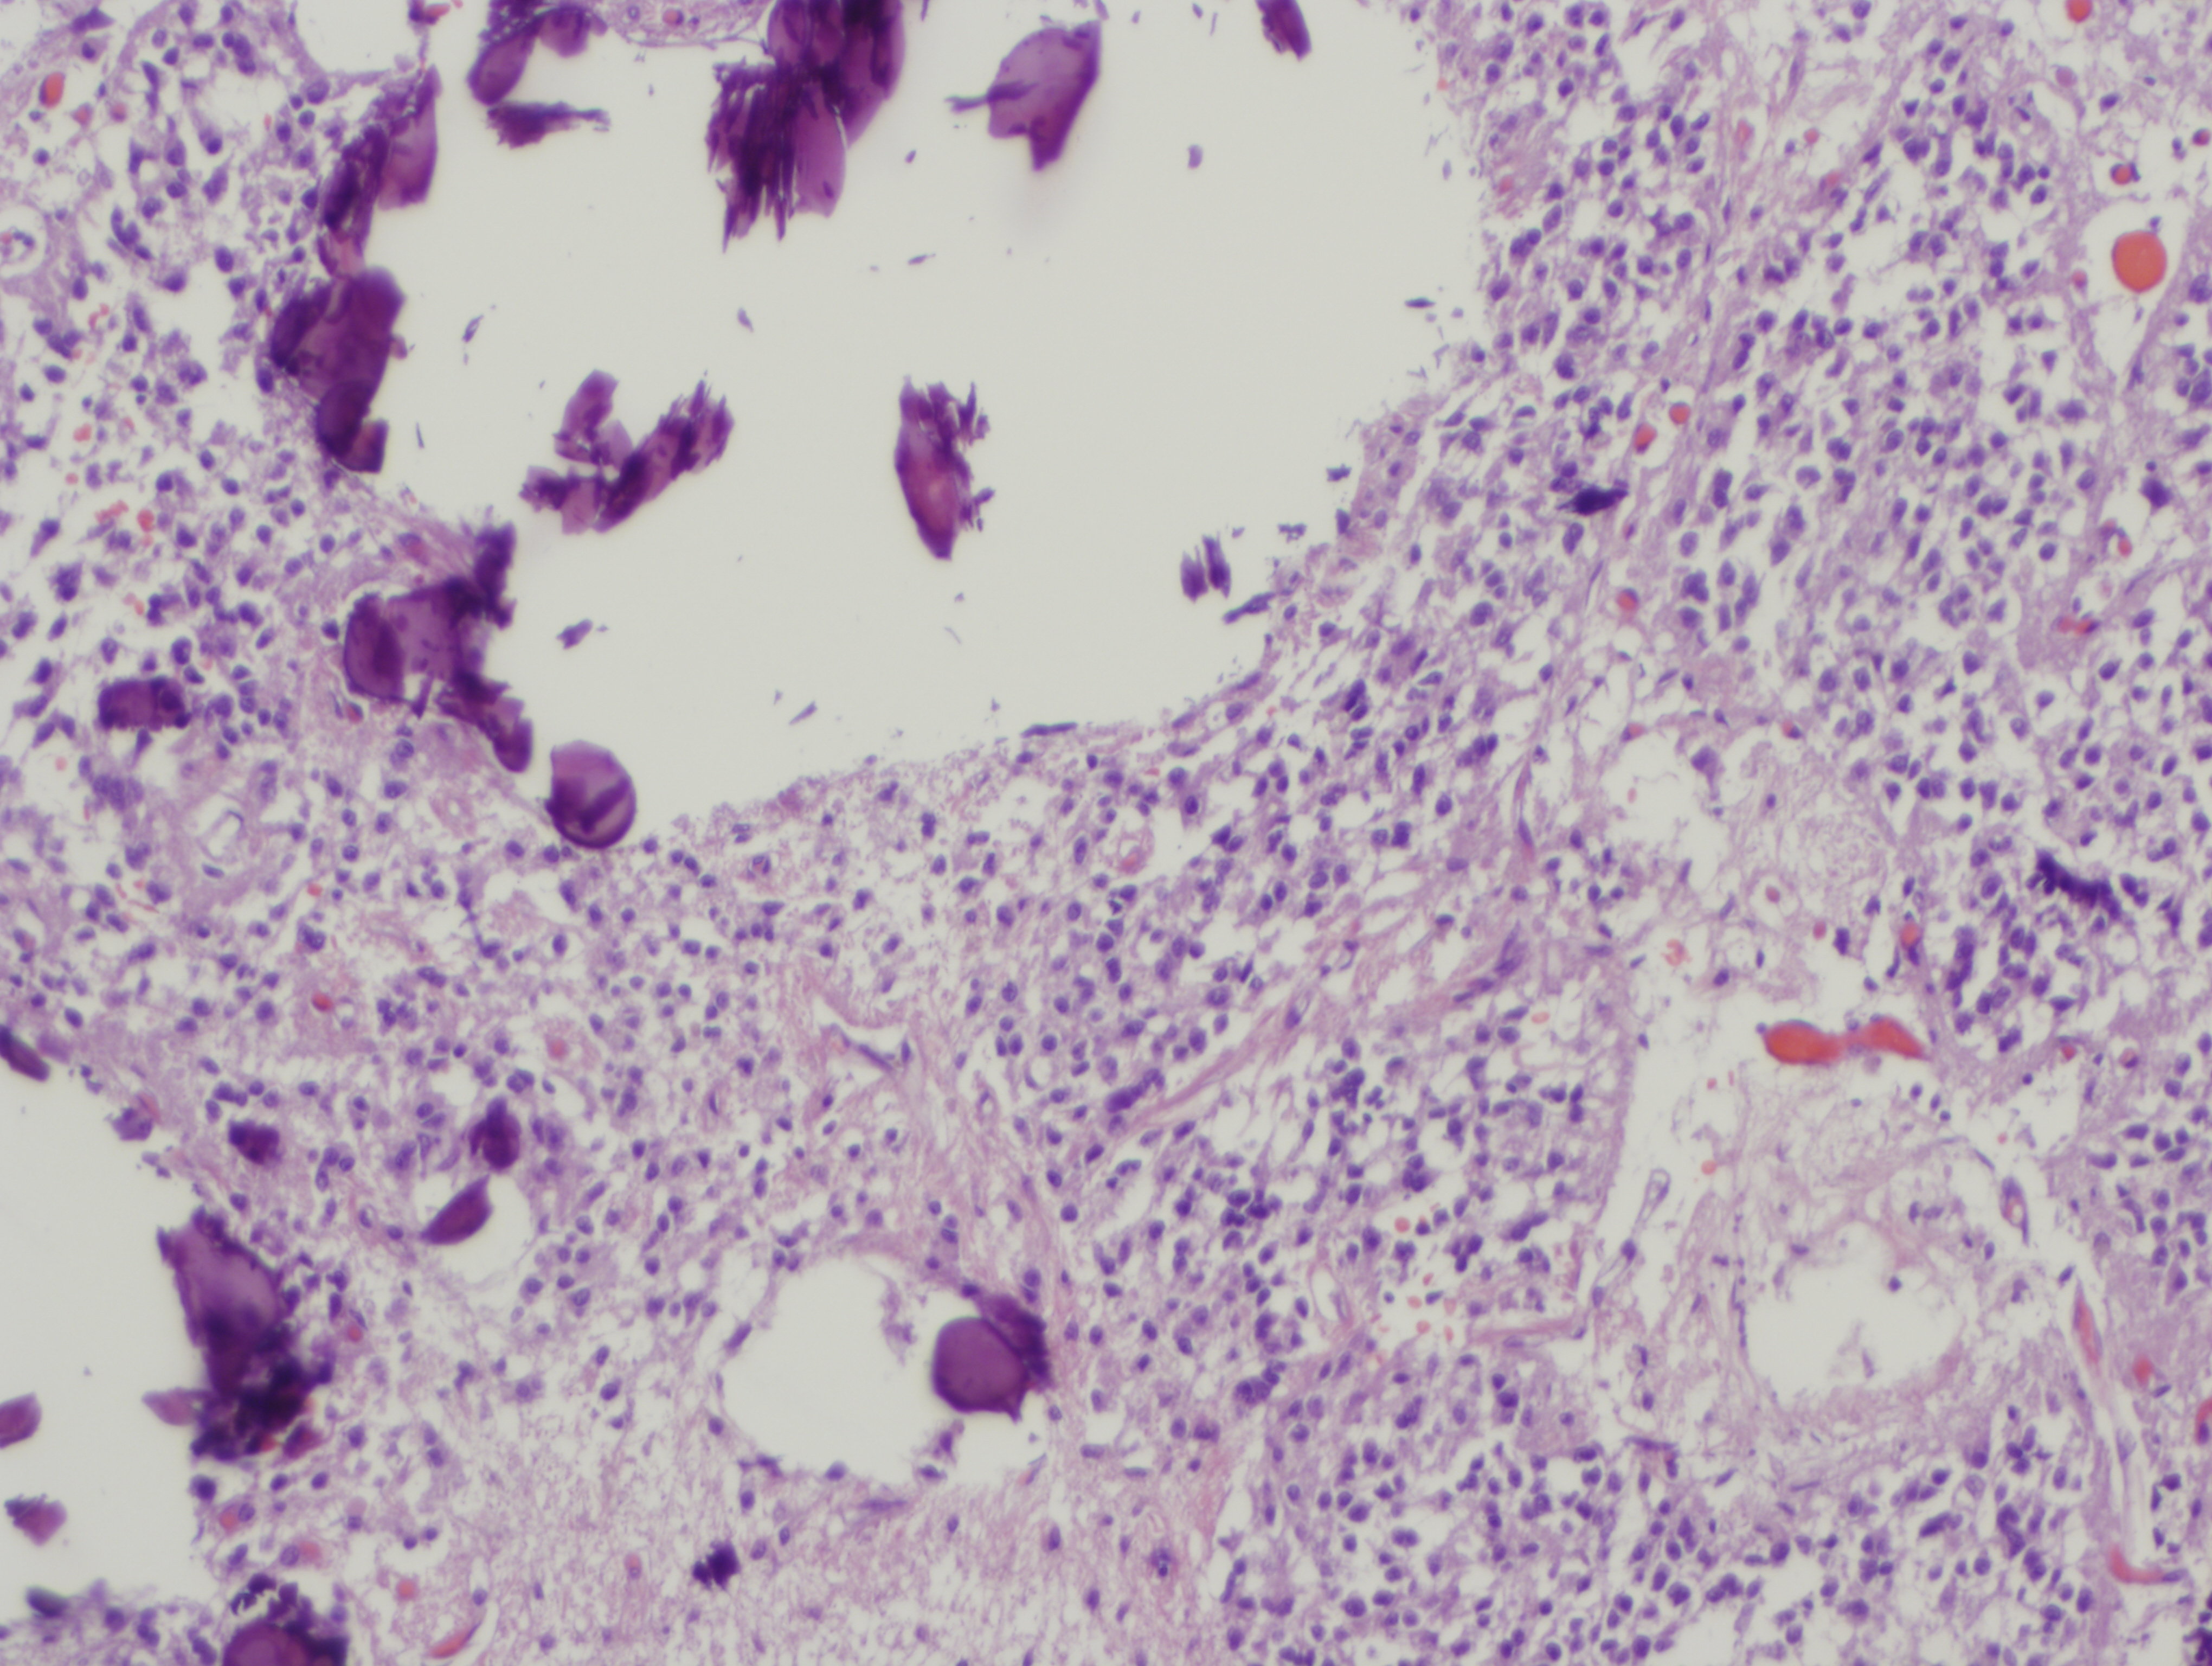

뇌, 특히 송과샘의 몇몇 부위에서는 칼슘 구조가 관찰되는데, 소위 ‘뇌모래(brain sand)’라 불리는 중추신경 조직에 존재하는 모래 상태의 물질이 바로 그것이다. 뇌모래는 나이가 들어감에 따라 그 수가 비례하여 증가하는 경향을 보인다. 화학적 분석 결과 뇌모래는 인산칼슘, 탄산칼슘, 인산암모늄으로 구성되어 있으며,[89] 2002년에 송과샘 내부 탄산칼슘 형태의 방해석 퇴적물로써 처음 보고되었다.[90] 송과샘 내부의 칼슘과 인의 퇴적은 노화와 밀접한 관련이 있다.

뇌와 특히 송과샘의 몇몇 부위에서는 '뇌모래(brain sand)'라 불리는 모래 형태의 물질이 관찰되는데, 이는 칼슘 구조로 이루어져 있다. 뇌모래는 나이가 들수록 그 수가 증가하는 경향이 있다. 화학 분석 결과, 뇌모래는 인산칼슘, 탄산칼슘, 인산암모늄으로 구성되어 있다는 것이 밝혀졌다.[89] 2002년에는 송과샘 내부에서 방해석 형태의 탄산칼슘 퇴적물이 처음으로 보고되었다.[90] 송과샘 내부의 칼슘과 인의 퇴적은 노화와 밀접한 관련이 있다.송과선 석회화는 젊은 성인에게서도 흔하게 나타나며, 심지어 두 살 정도의 어린이에게서도 관찰된다.[35] 송과선 석회화는 멜라토닌[37][38] 합성을 방해하여 수면 문제를 일으킬 수 있다는 주장이 있지만, 이에 대한 과학적 결론은 아직 내려지지 않은 상태이다.[39][40]